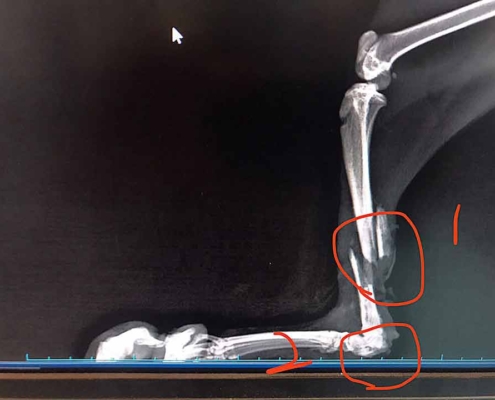

看著貓兒慵懶的模樣,可知他一個多月前,乾瘦無力,骨折、肌肉糜爛,卻被庸醫要求沒有經驗的救援人自行帶回照顧,等養胖一點再過來……!

貓兒雖然飢餓又重傷,卻超級親人!我們緊急送醫,打針吃藥、打骨釘、住院…… 一週後,愛生知道園區經濟拮据,認為我們有照護的能力,為了幫助節約,就讓我們帶回照顧了!

灰灰預訂七月初就可以拆除骨釘了,這個曾經一路坎坷的孩子,準備展開歡顏迎接新的《貓生》啦!